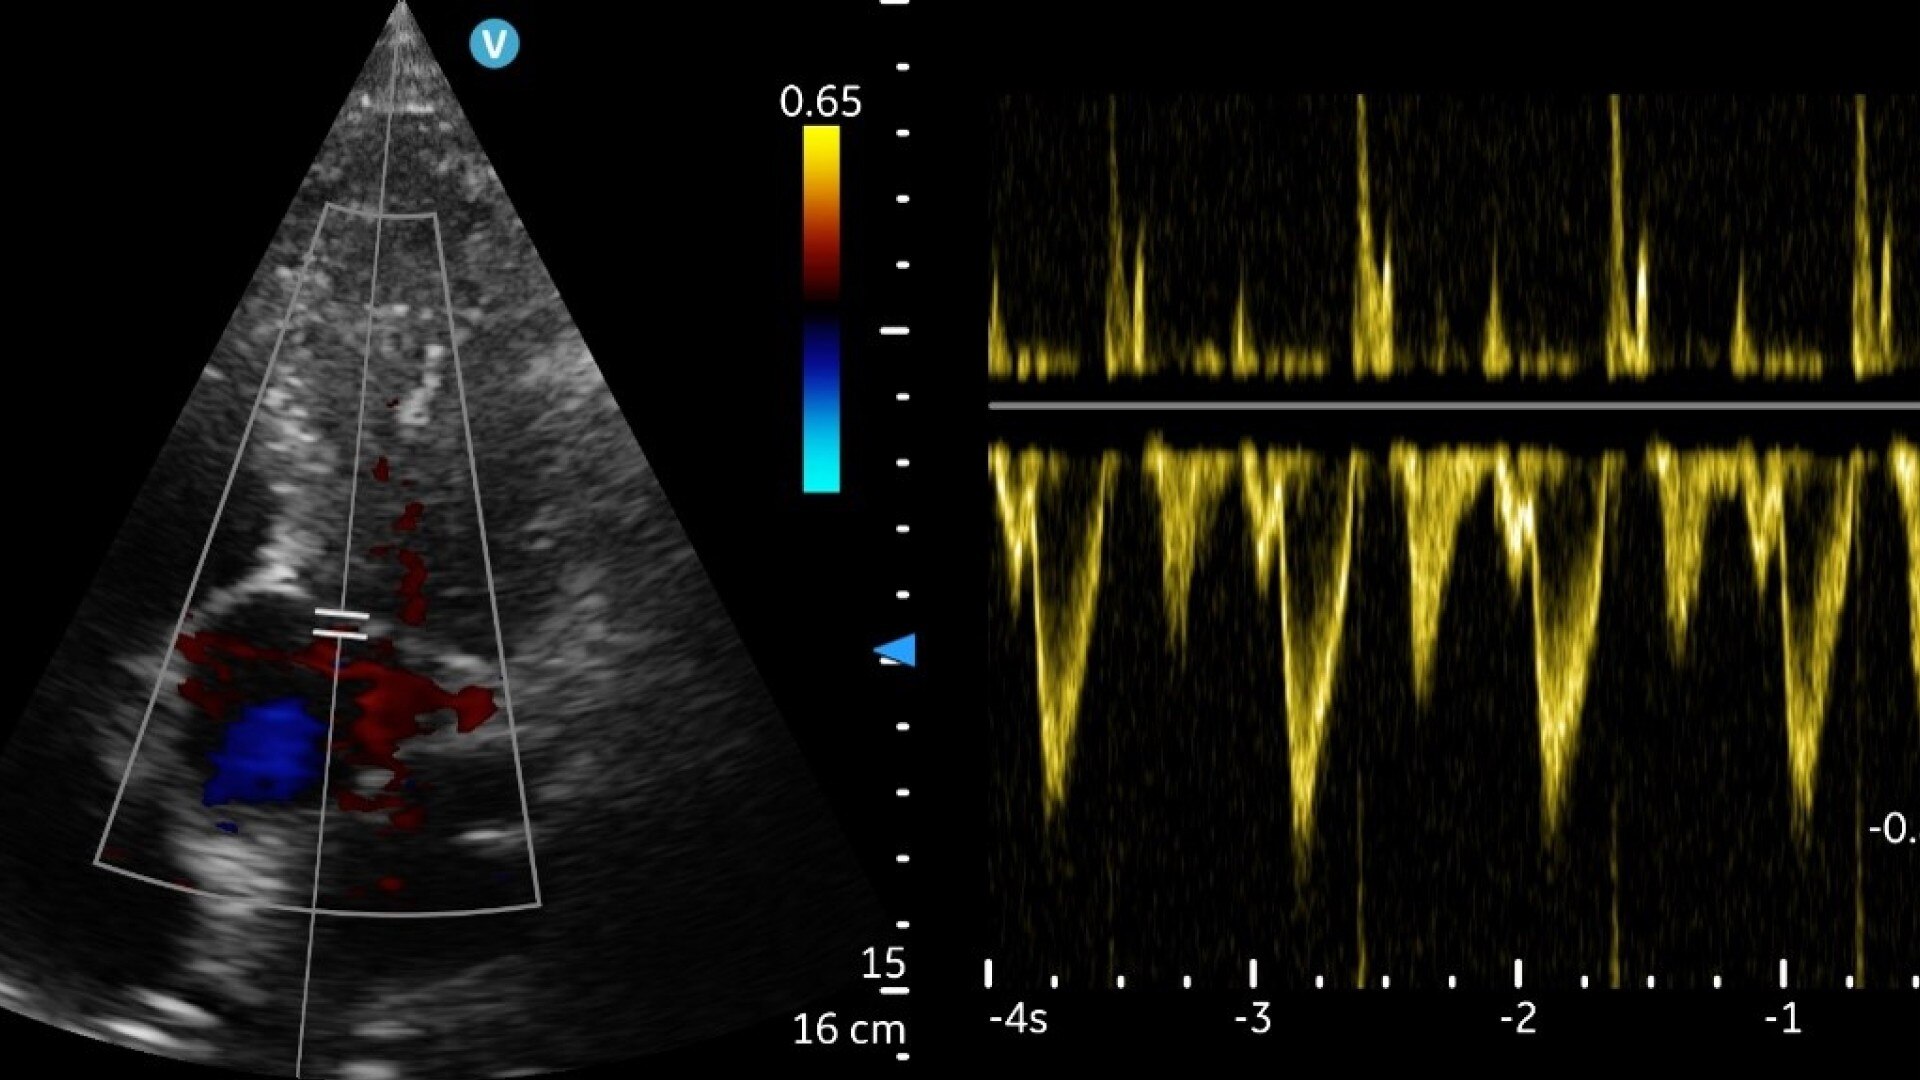

« Flow Profiles est une fonction que j'apprécie vraiment et dont je ne peux plus me passer. Elle nous permet de rationaliser l'acquisition de profils Doppler de très haute qualité à partir des différentes structures vasculaires et cardiaques, ce qui rend l'optimisation de l'image très rapide. »

Dr. Elena Sinkovskaya

Eastern Virginia Medical School - Virginie, États-Unis